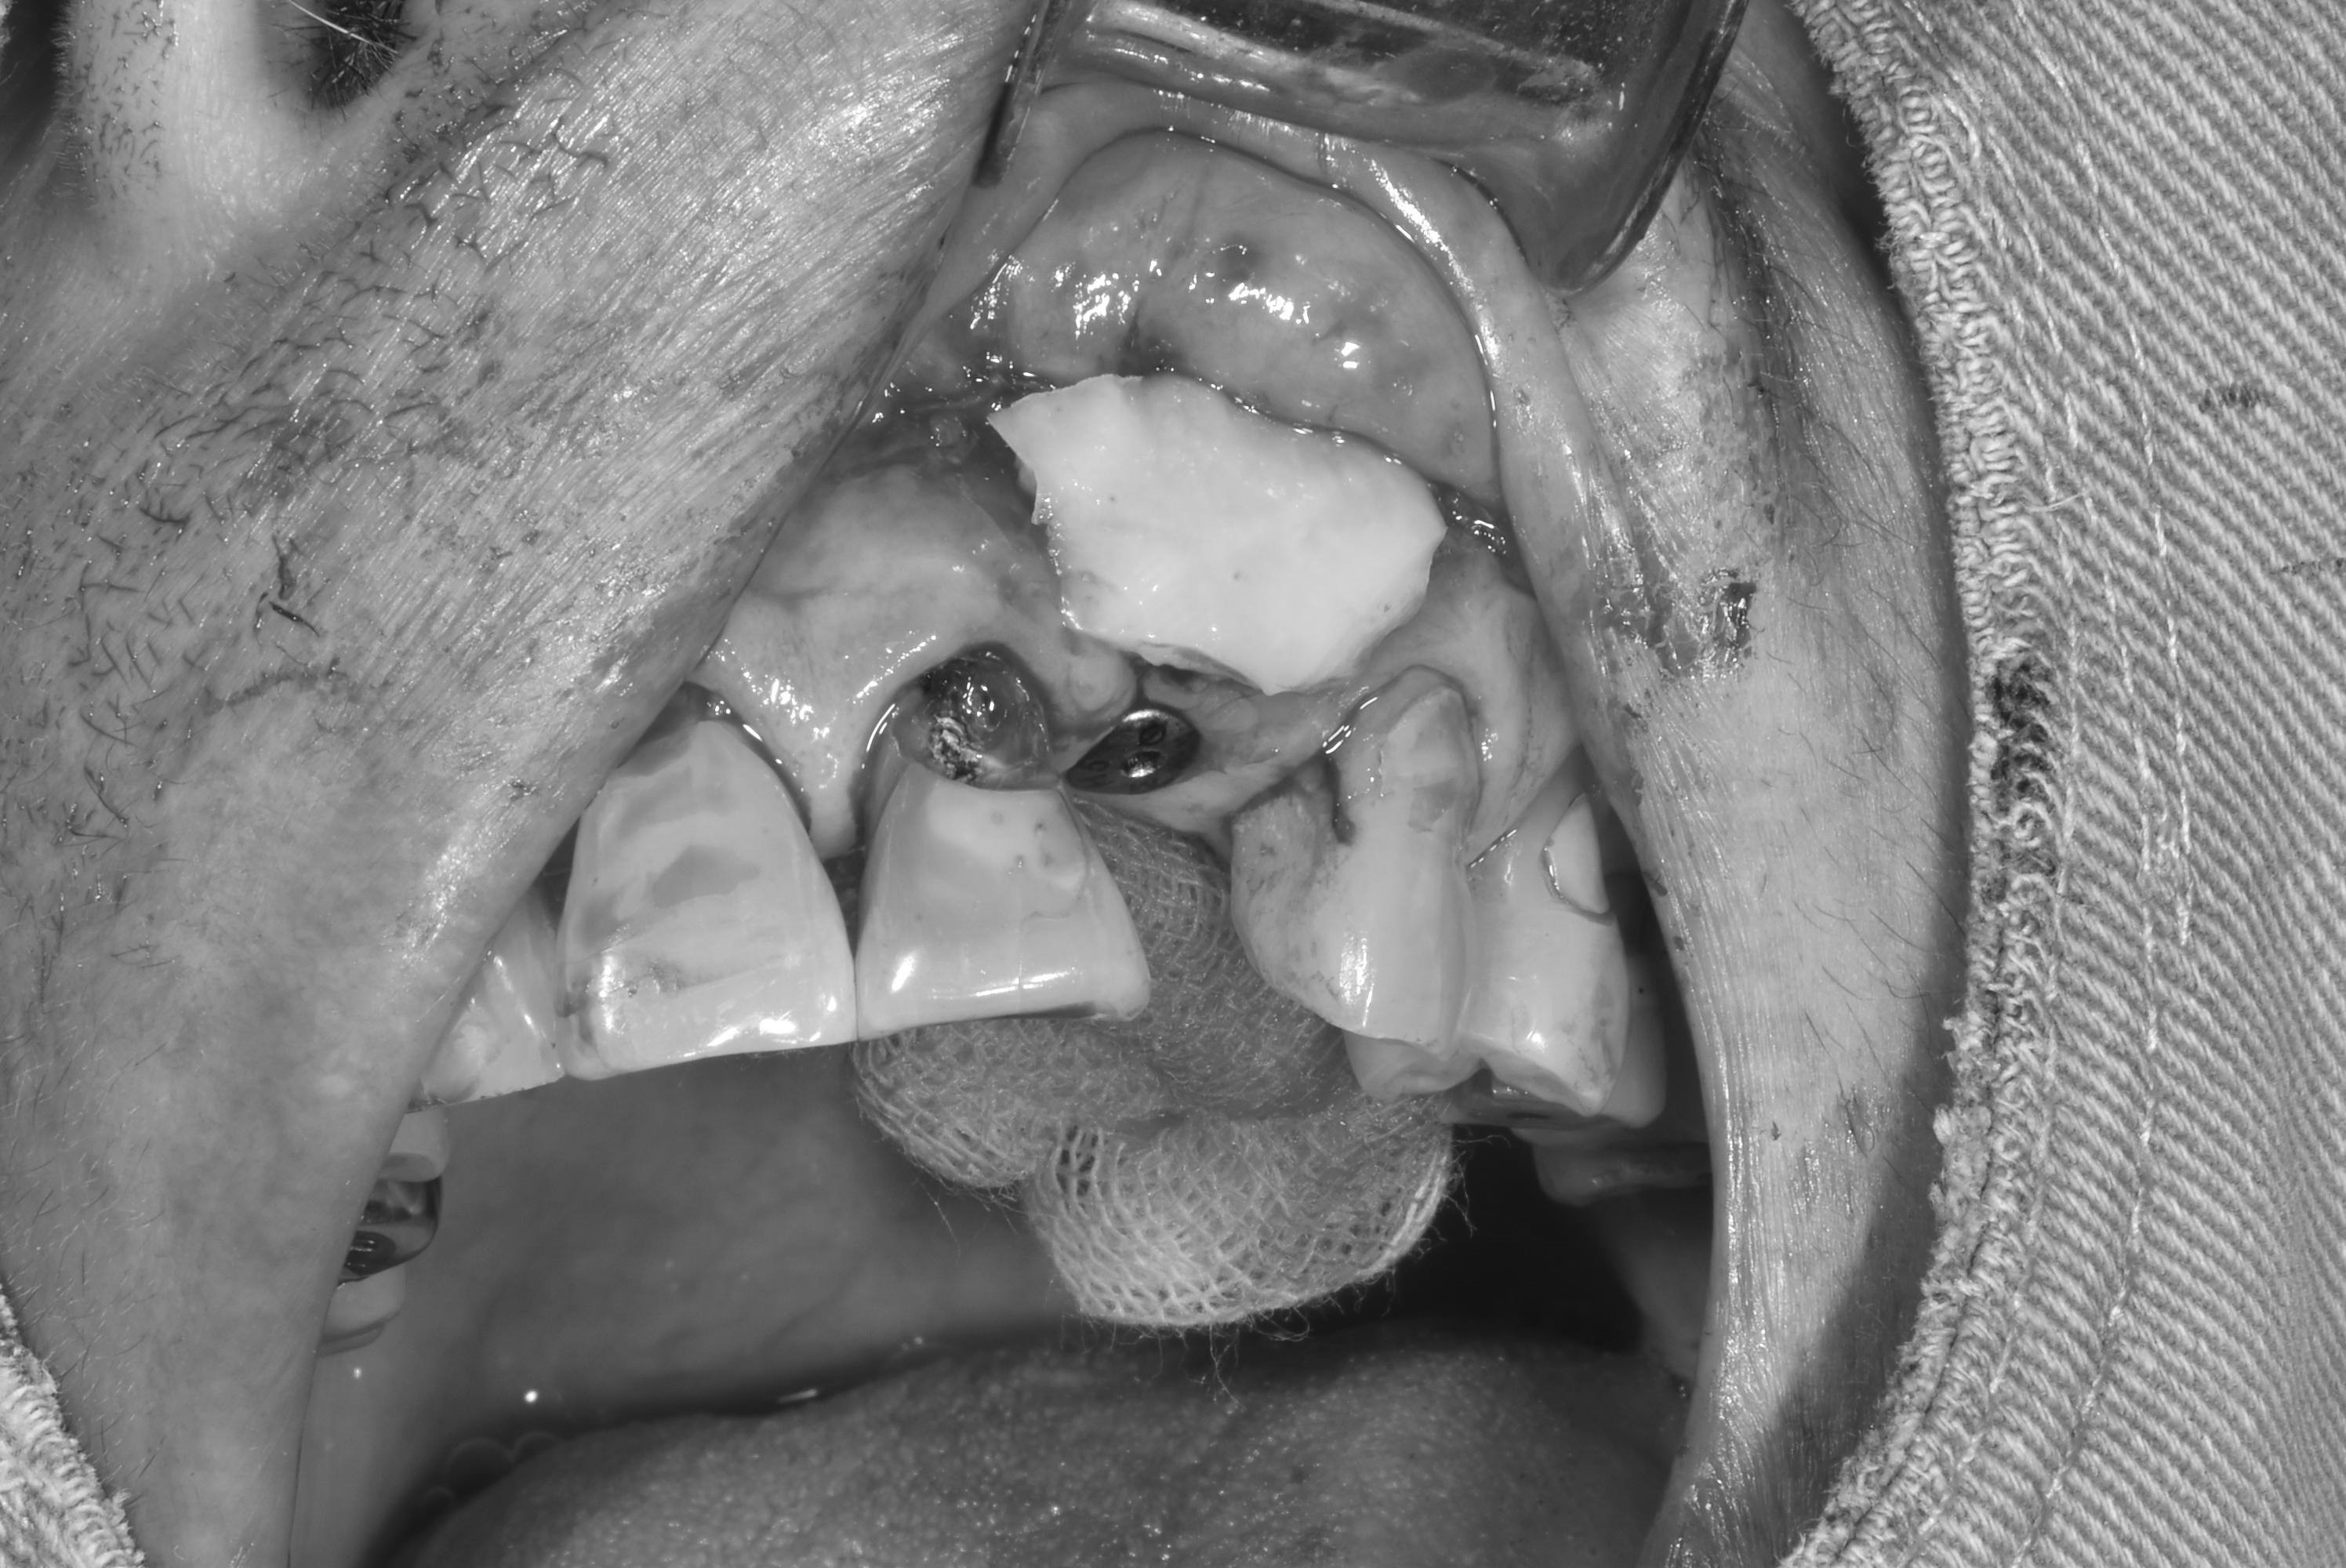

案例三